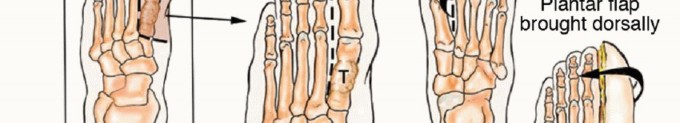

* أنواع البتر في القدم:

* البتر الجزئي للقدم (Partial Foot Amputation): يشمل إزالة جزء من القدم (مثل إصبع واحد، أو عدة أصابع، أو جزء من الأمشاط). يمكن للمرضى غالبًا المشي بشكل جيد باستخدام أحذية خاصة أو أطراف صناعية جزئية.

* البتر عبر الكاحل (Ankle Disarticulation/Syme Amputation): إزالة القدم عند مفصل الكاحل. يسمح هذا النوع بتحمل الوزن على طرف الكاحل المتبقي ويوفر قاعدة جيدة للطرف الصناعي.

* البتر تحت الركبة (Transtibial Amputation): في حالات الأورام الأكثر انتشارًا، قد يكون من الضروري بتر الساق تحت الركبة. يركز الدكتور هطيف على الحفاظ على أكبر قدر ممكن من الساق لتمكين استخدام الأطراف الصناعية المتقدمة.

* النهج الحديث في البتر: يستخدم الدكتور هطيف أحدث التقنيات لضمان بتر نظيف، وتقليل المضاعفات، وتهيئة الطرف المتبقي بشكل مثالي لتركيب الأطراف الصناعية.